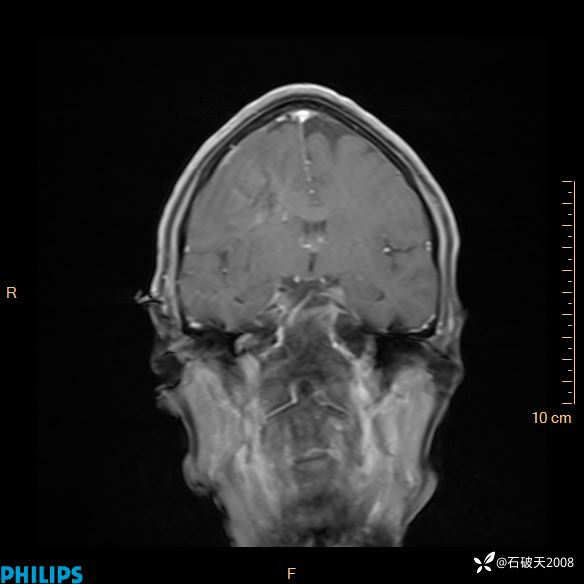

2020.11.14MR

增强冠状位